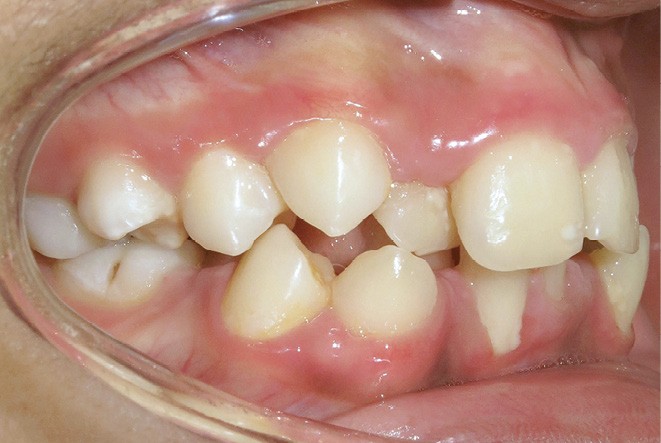

Le niveau d’hygiène est alarmant, car le rituel du brossage des dents n’est pas instauré dans la famille. Des caries se sont développées sur les dents temporaires et en ont imposé l’extraction. Les molaires permanentes ont dérivé mésialement, réduisant l’espace disponible sur l’arcade.

En denture adulte, la DDM est majeure avec un déficit de place estimé de 13 mm à la mandibule. Les lésions carieuses ont aussi touché les premières molaires permanentes maxillaires. La 26 a été avulsée et la 27 a pris sa place. Côté controlatéral, la 16 est fortement délabrée, rendant impossible sa conservation. Les molaires ayant plus mésialé à l’arcade mandibulaire, les rapports occlusaux sont de classe III. Les incisives sont versées vers l’avant, mais nous pouvons considérer qu‘il s’agit d’une biproalvéolie ethnique. Du point de vue squelettique, le patient présente une classe II squelettique par rétromandibulie sur un schéma facial hyperdivergent (fig. 1a-j).